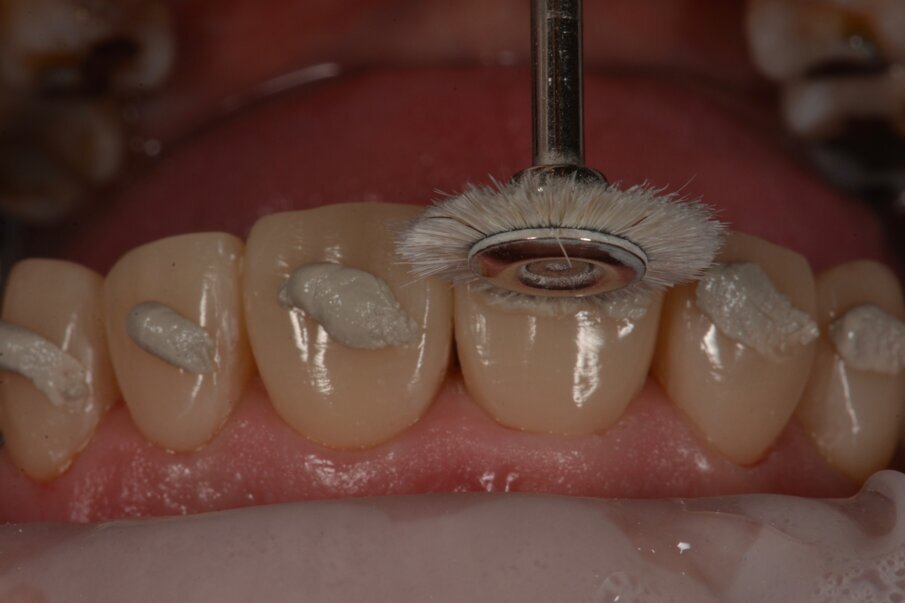

Hoogglans werd bereikt door met de paarse 3MTM Sof-LexTM Spiral te polijsten met hoog toerental met waterkoeling gedurende 5-10 minuten.

Indien gewenst kan nog worden nagepolijst met een diamantpasta en een geitenhaar borstel.